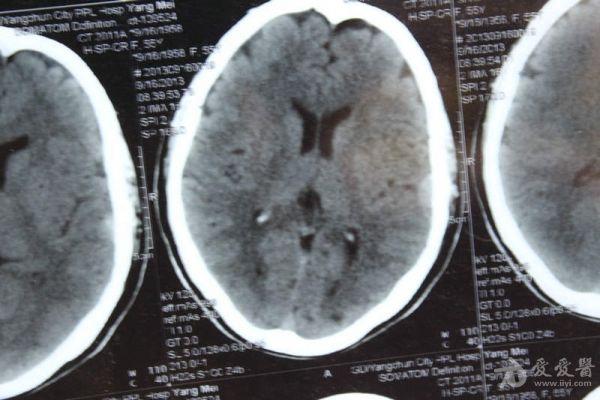

脑部占位病变CT,MRI图片,请帮忙诊断

最近感图样,无其它脑病病史

考虑脑膜瘤!!

磁共振没有平扫,增强矢状位没找到病灶。像脑膜瘤。

图片不是很清楚,应该是脑膜瘤!